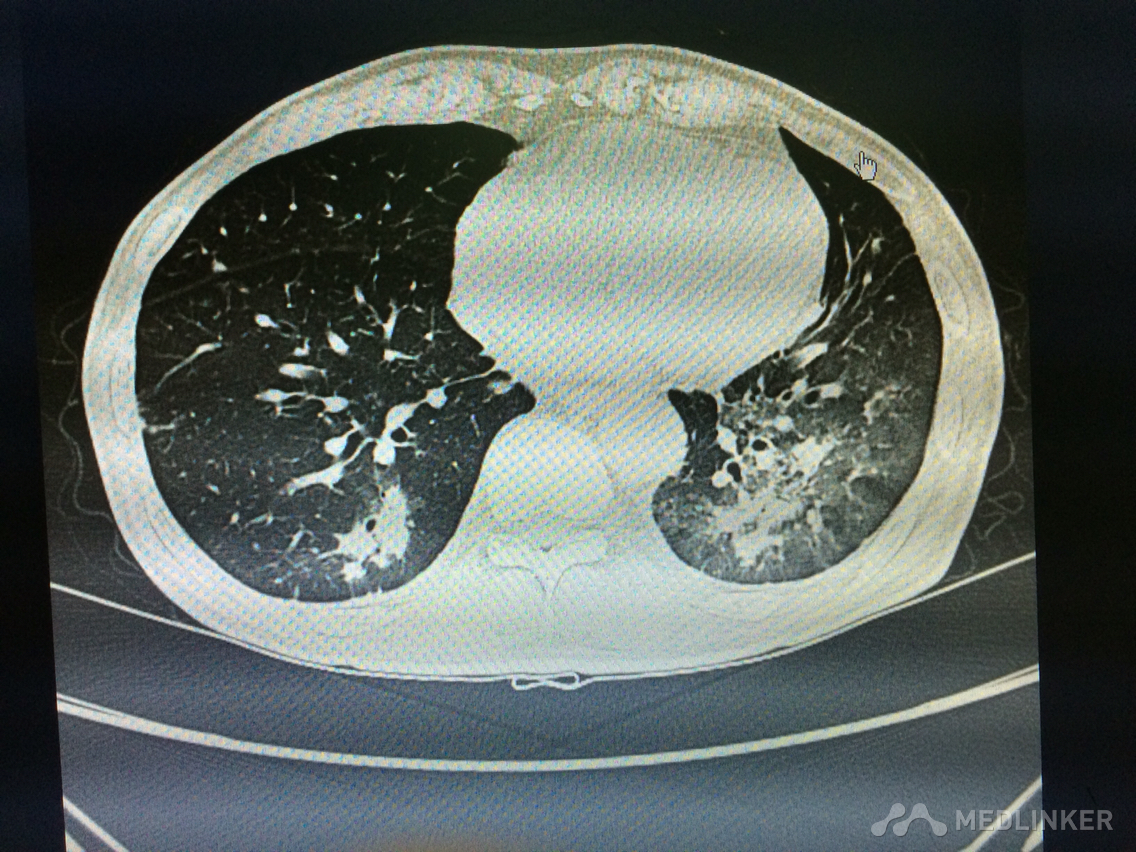

看这胸部CT?

咳嗽咳痰发热3天,伴胸痛气紧,偶痰中带血,体温38.7,伴全身乏力。

胸部!CT,,考虑什么?